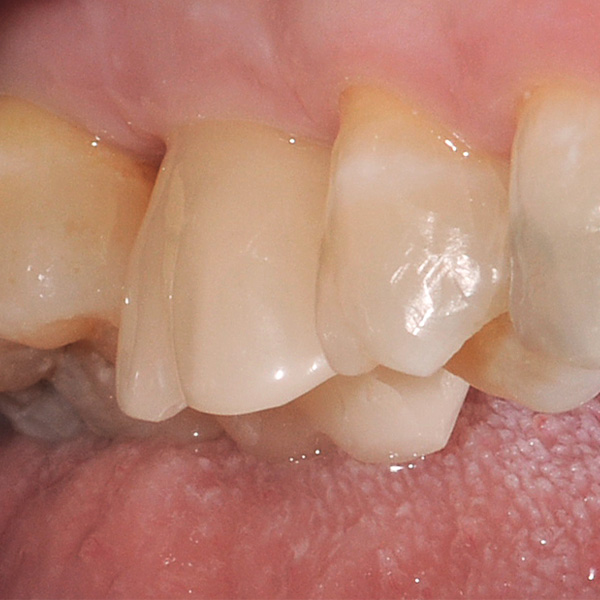

Sobre todo las restauraciones sobre implantes están sometidas a elevadas solicitaciones. Tras la extracción y el implante, al paciente le falta el tejido fibroso elástico del lecho dental natural. En consecuencia, no se absorben las fuerzas oclusales, sino que se transmiten directamente a la restauración, al implante, al hueso y a los dientes antagonistas. La cerámica híbrida VITA ENAMIC incorpora una matriz dual de cerámica (86 % del peso) y polímero (14 % del peso). Esto le otorga una elasticidad similar a la de la dentina y la capacidad de absorber fuerzas oclusales. Gracias a su elevada dimensión vertical, la pieza en bruto policroma VITA ENAMIC multiColor en la geometría EMC-16 posibilita, incluso en caso de hueso atrofiado, la confección de coronas sobre pilar monolíticas de una pieza. El doctor y catedrático Alexander Hassel muestra en el siguiente artículo cómo ha tratado a una paciente empleando este método de restauración.